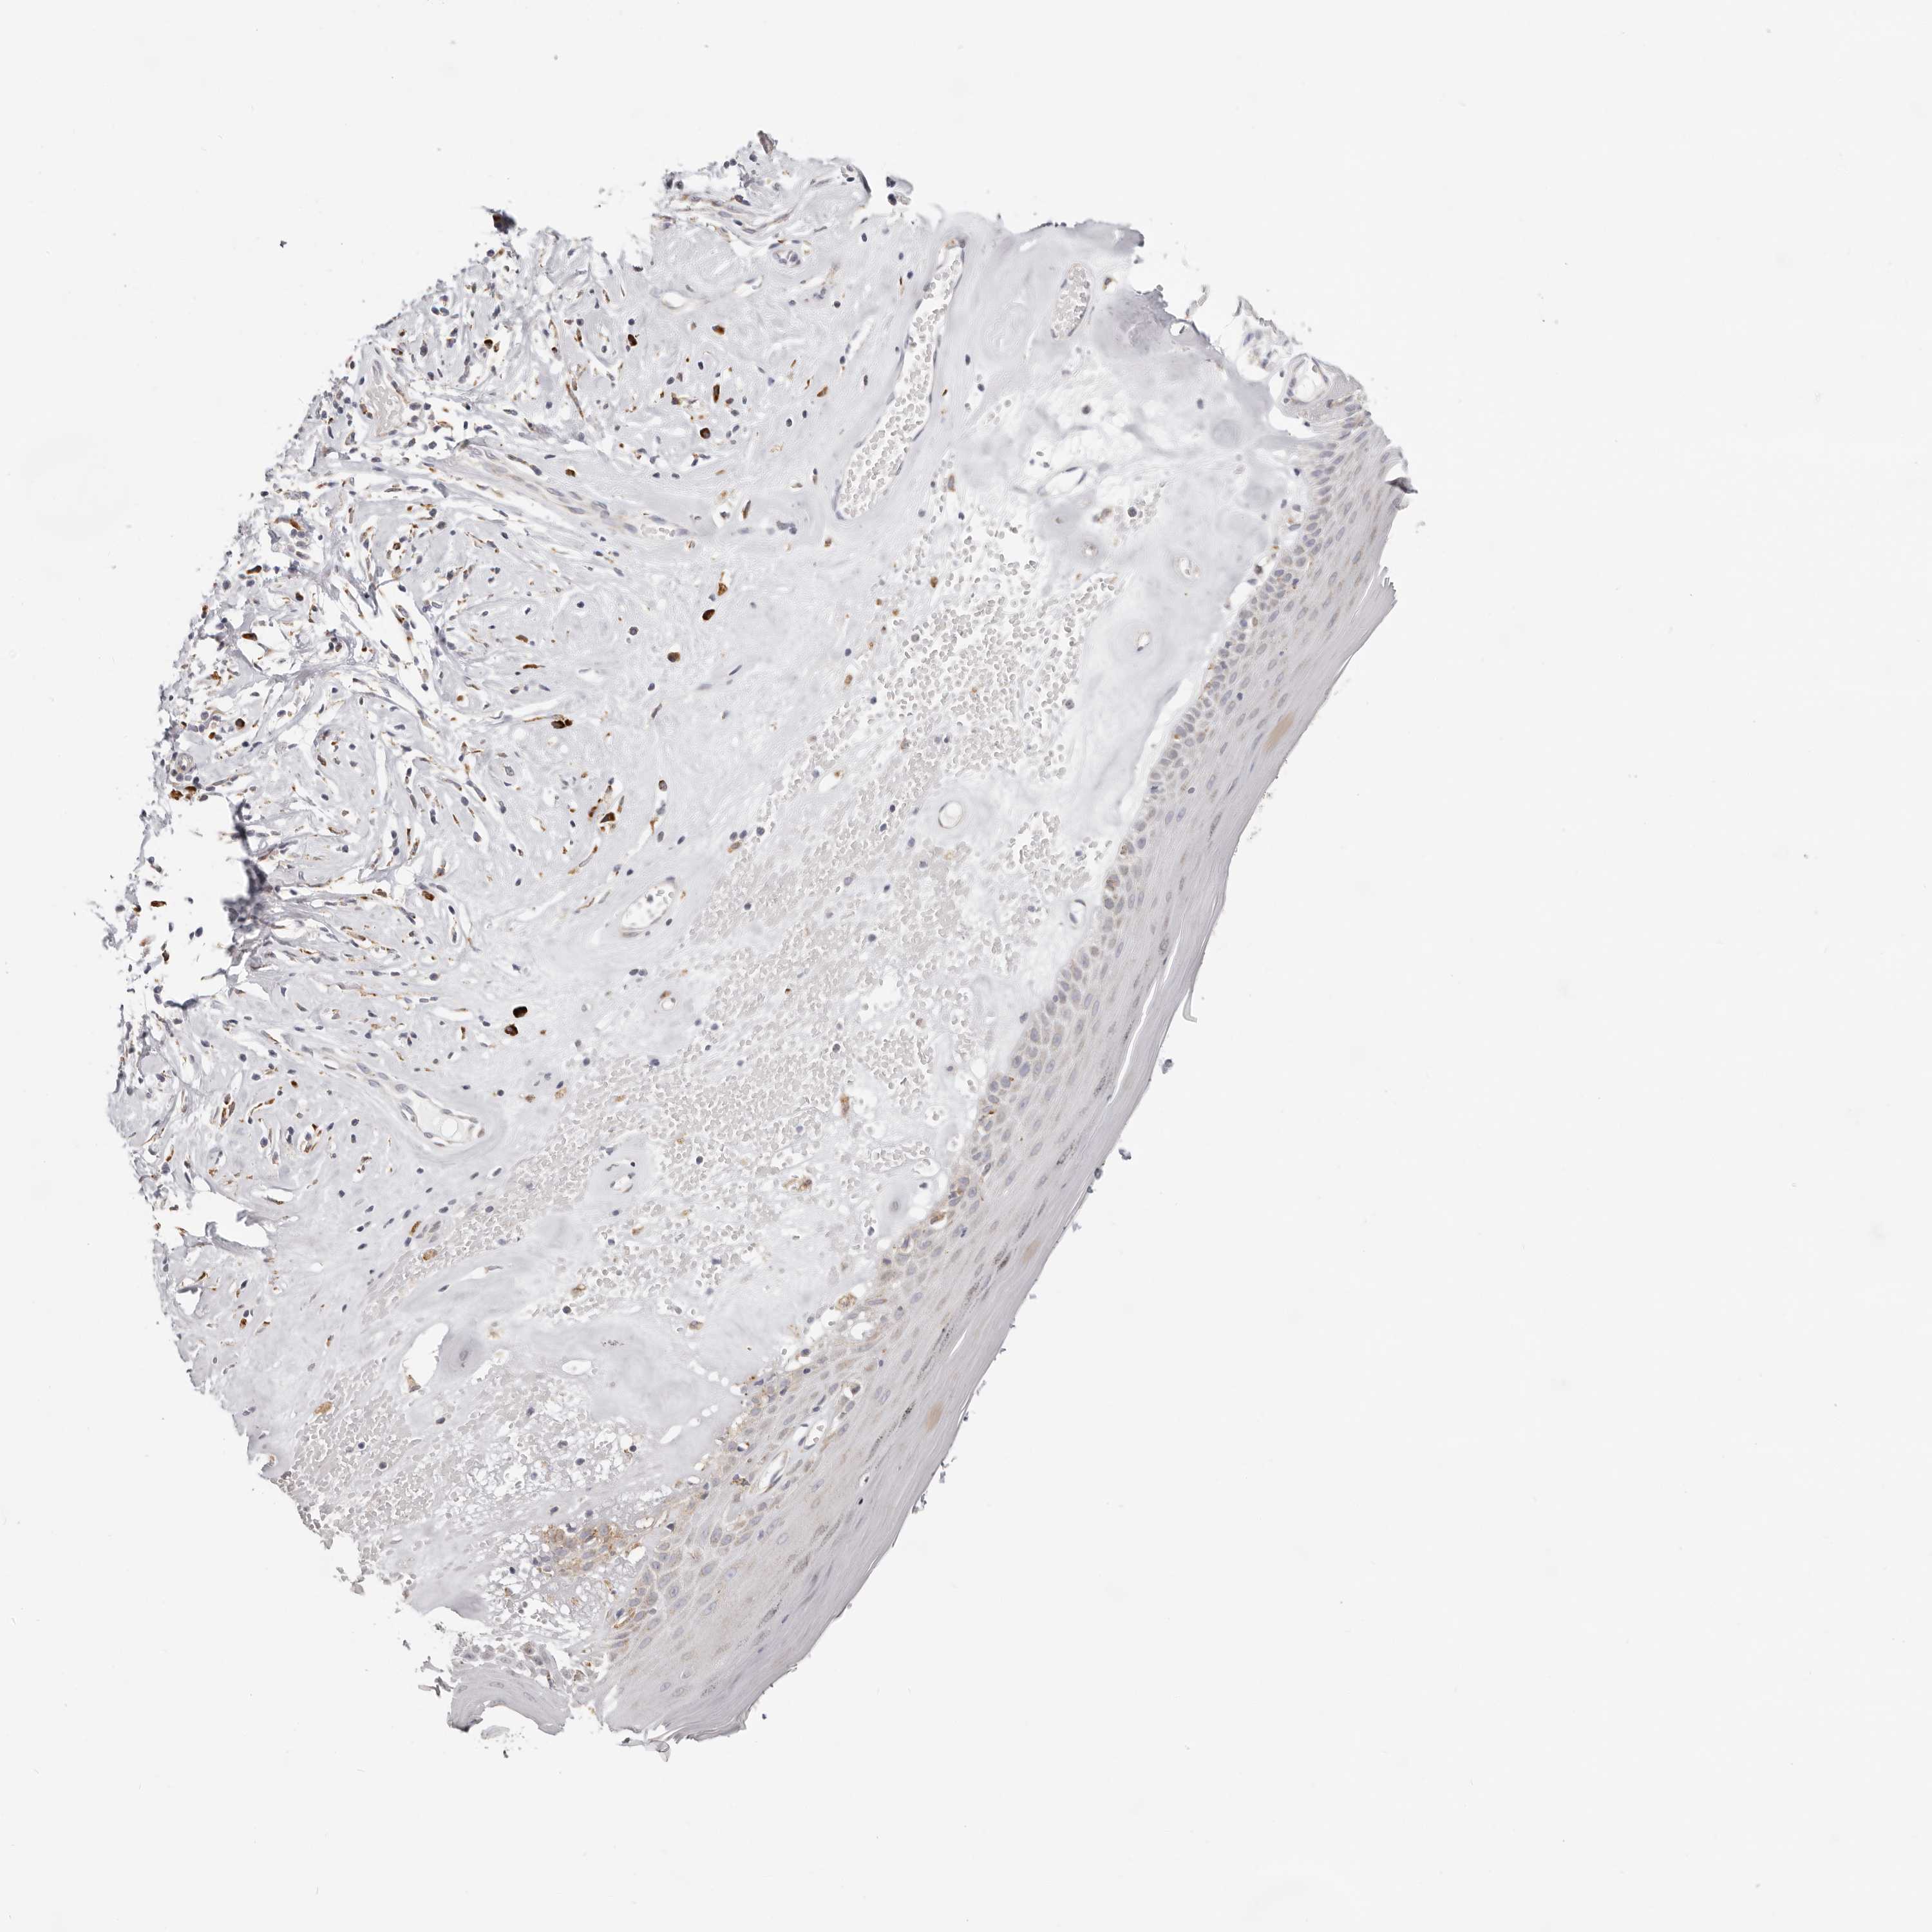

SKIN 1 - Antibody stainingi

Antibody staining in the annotated cell types in the current human tissue is reported as not detected, low, medium, or high, based on conventional immunohistochemistry profiling in selected tissues. This score is based on the combination of the staining intensity and fraction of stained cells.

Each image is clickable and will lead to virtual microscopy that enables deeper exploration of all samples and also displays staining intensity scores, fraction scores and subcellular localization as well as patient and tissue information for each sample.

Antibody HPA029397Antibody CAB030029

Langerhans MediumNot detected

Fibroblasts Not detectedLow

Keratinocytes MediumNot detected

Melanocytes MediumLow